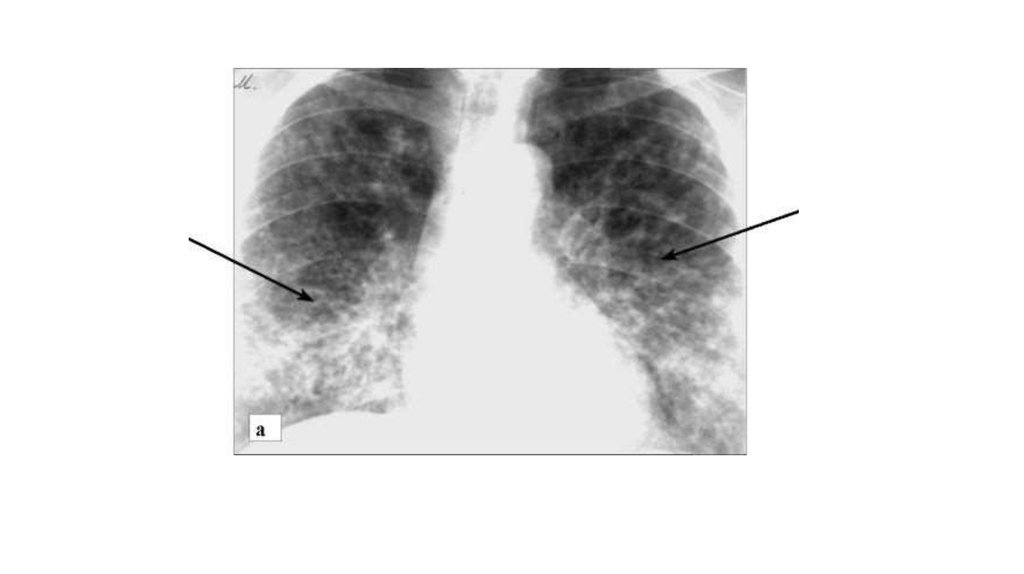

• Саркоидоз, 2-я стадия. Определяется двусторонняя симметричная

мелкоочаговая перилимфатическая диссеминация (стрелки),

корни легких расширены за счет увеличенных лимфоузлов: а рентгенограмма в прямой проекции